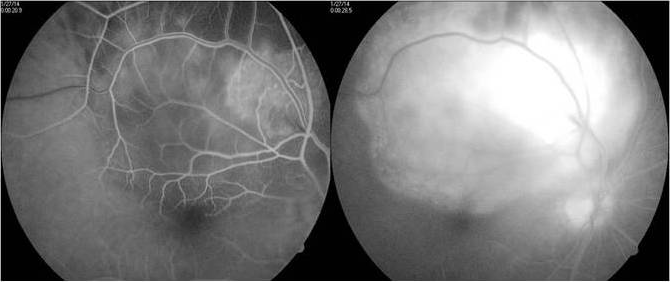

Fundus flourescein angiography showed an early hyperflourescence in the region of the lesion with progressive increase in hyperflourescence and pooling of the dye outlining the serous detachment by late phases (Figure 2 [Fig. 2]). Ultrasonography showed a mass lesion of uniform echogenecity with low internal reflectivity (Figure 3 [Fig. 3]).

Figure 2: FFA shows early hyperflourescence with late pooling in serous detachment.

At ten-month follow-up, the scarred granuloma was stable with a visual acuity of 6/12p. A month later, still on ATT, the patient reported diminution of vision in the right eye, with best corrected visual acuity (BCVA) falling to 6/36p in RE. RE fundus examination showed macular edema with subretinal blood and exudates adjacent to the scar of the previous choroidal granuloma (Figure 8 [Fig. 8]). Fundus fluorescein angiography (FFA) showed patchy hypoflourescence due to subretinal blood and exudates and mild diffuse late leakage due to juxtafoveal CNVM. Spectral domain optical coherence tomography (SD-OCT) showed an increased foveal thickness, a dome-shaped hyperreflectivity at the level of the retinal pigment epithelium (RPE) and adjacent intraretinal cystic changes indicative of an active CNVM.

Figure 8: Juxtafoveal yellowish white lesion adjacent to healed scar with retinal edema, subretinal blood, exudates and subretinal fluid. FFA and SD-OCT showed signs of active choroidal neovascular membrane at the margin of the scar.